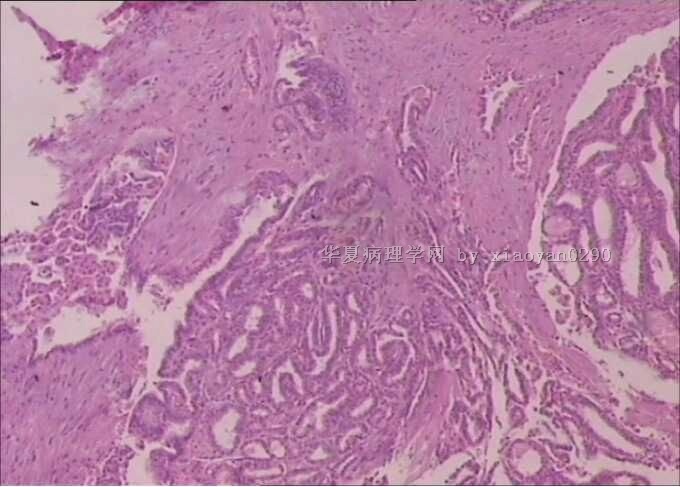

甲状腺乳头状癌?

姓    名: ××× 性别:  女 年龄:  55

标本名称:  气管旁肿物

肉眼检查:  甲状腺右侧肿物4x3x2,左侧3x3x1.5cm,结节状,

临床术中所见气管旁一肿物1x1,与气管粘连较重,该肿物与甲状腺也相连。

送检的左侧及右侧肿物均为结甲,良性病变。只是这一小块连接气管的一侧少部分呈现乳头样改变,其余部分也是正常的。最后一张图片不是这个病例的,不知道怎么删除。

够甲状腺乳头状癌了

甲状腺乳头状癌

本例最好做个CK19,CD10比较放心。